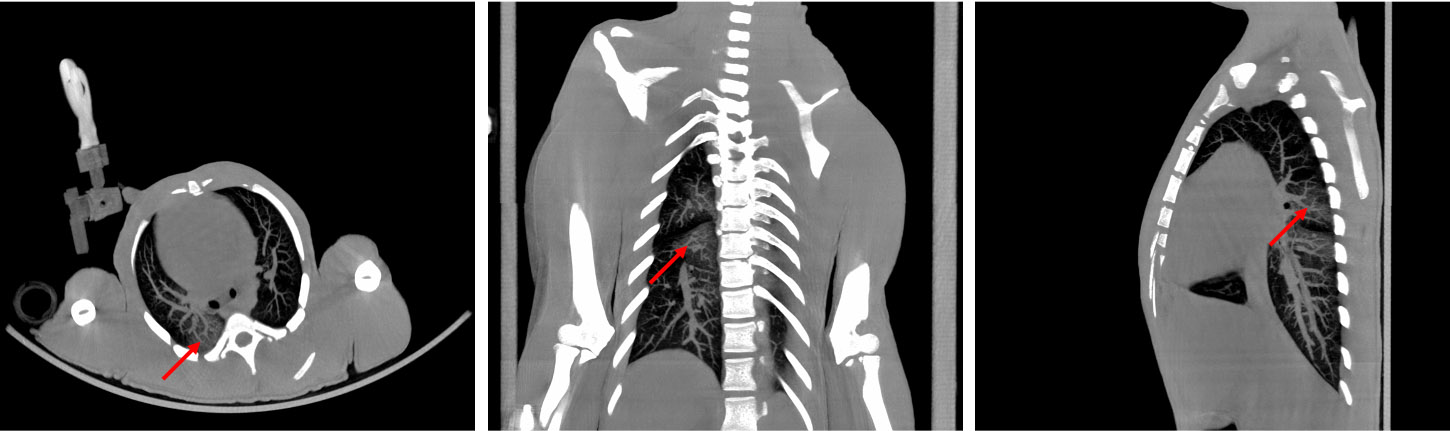

CASE: NHP CT lung imaging

• Courtesy of: University of Tours, Preclinical imaging department - PST ASB

Research objective: Investigation of lung inflammation in NHP

Animal model: Female Macaca fascicularis, 4.5 kg

Acquisition protocol: 80kV, 98s per bed, 2 bed positions

Processing and reconstruction protocol: 0.12 mm isotropic voxel size, iterative reconstruction algortihm